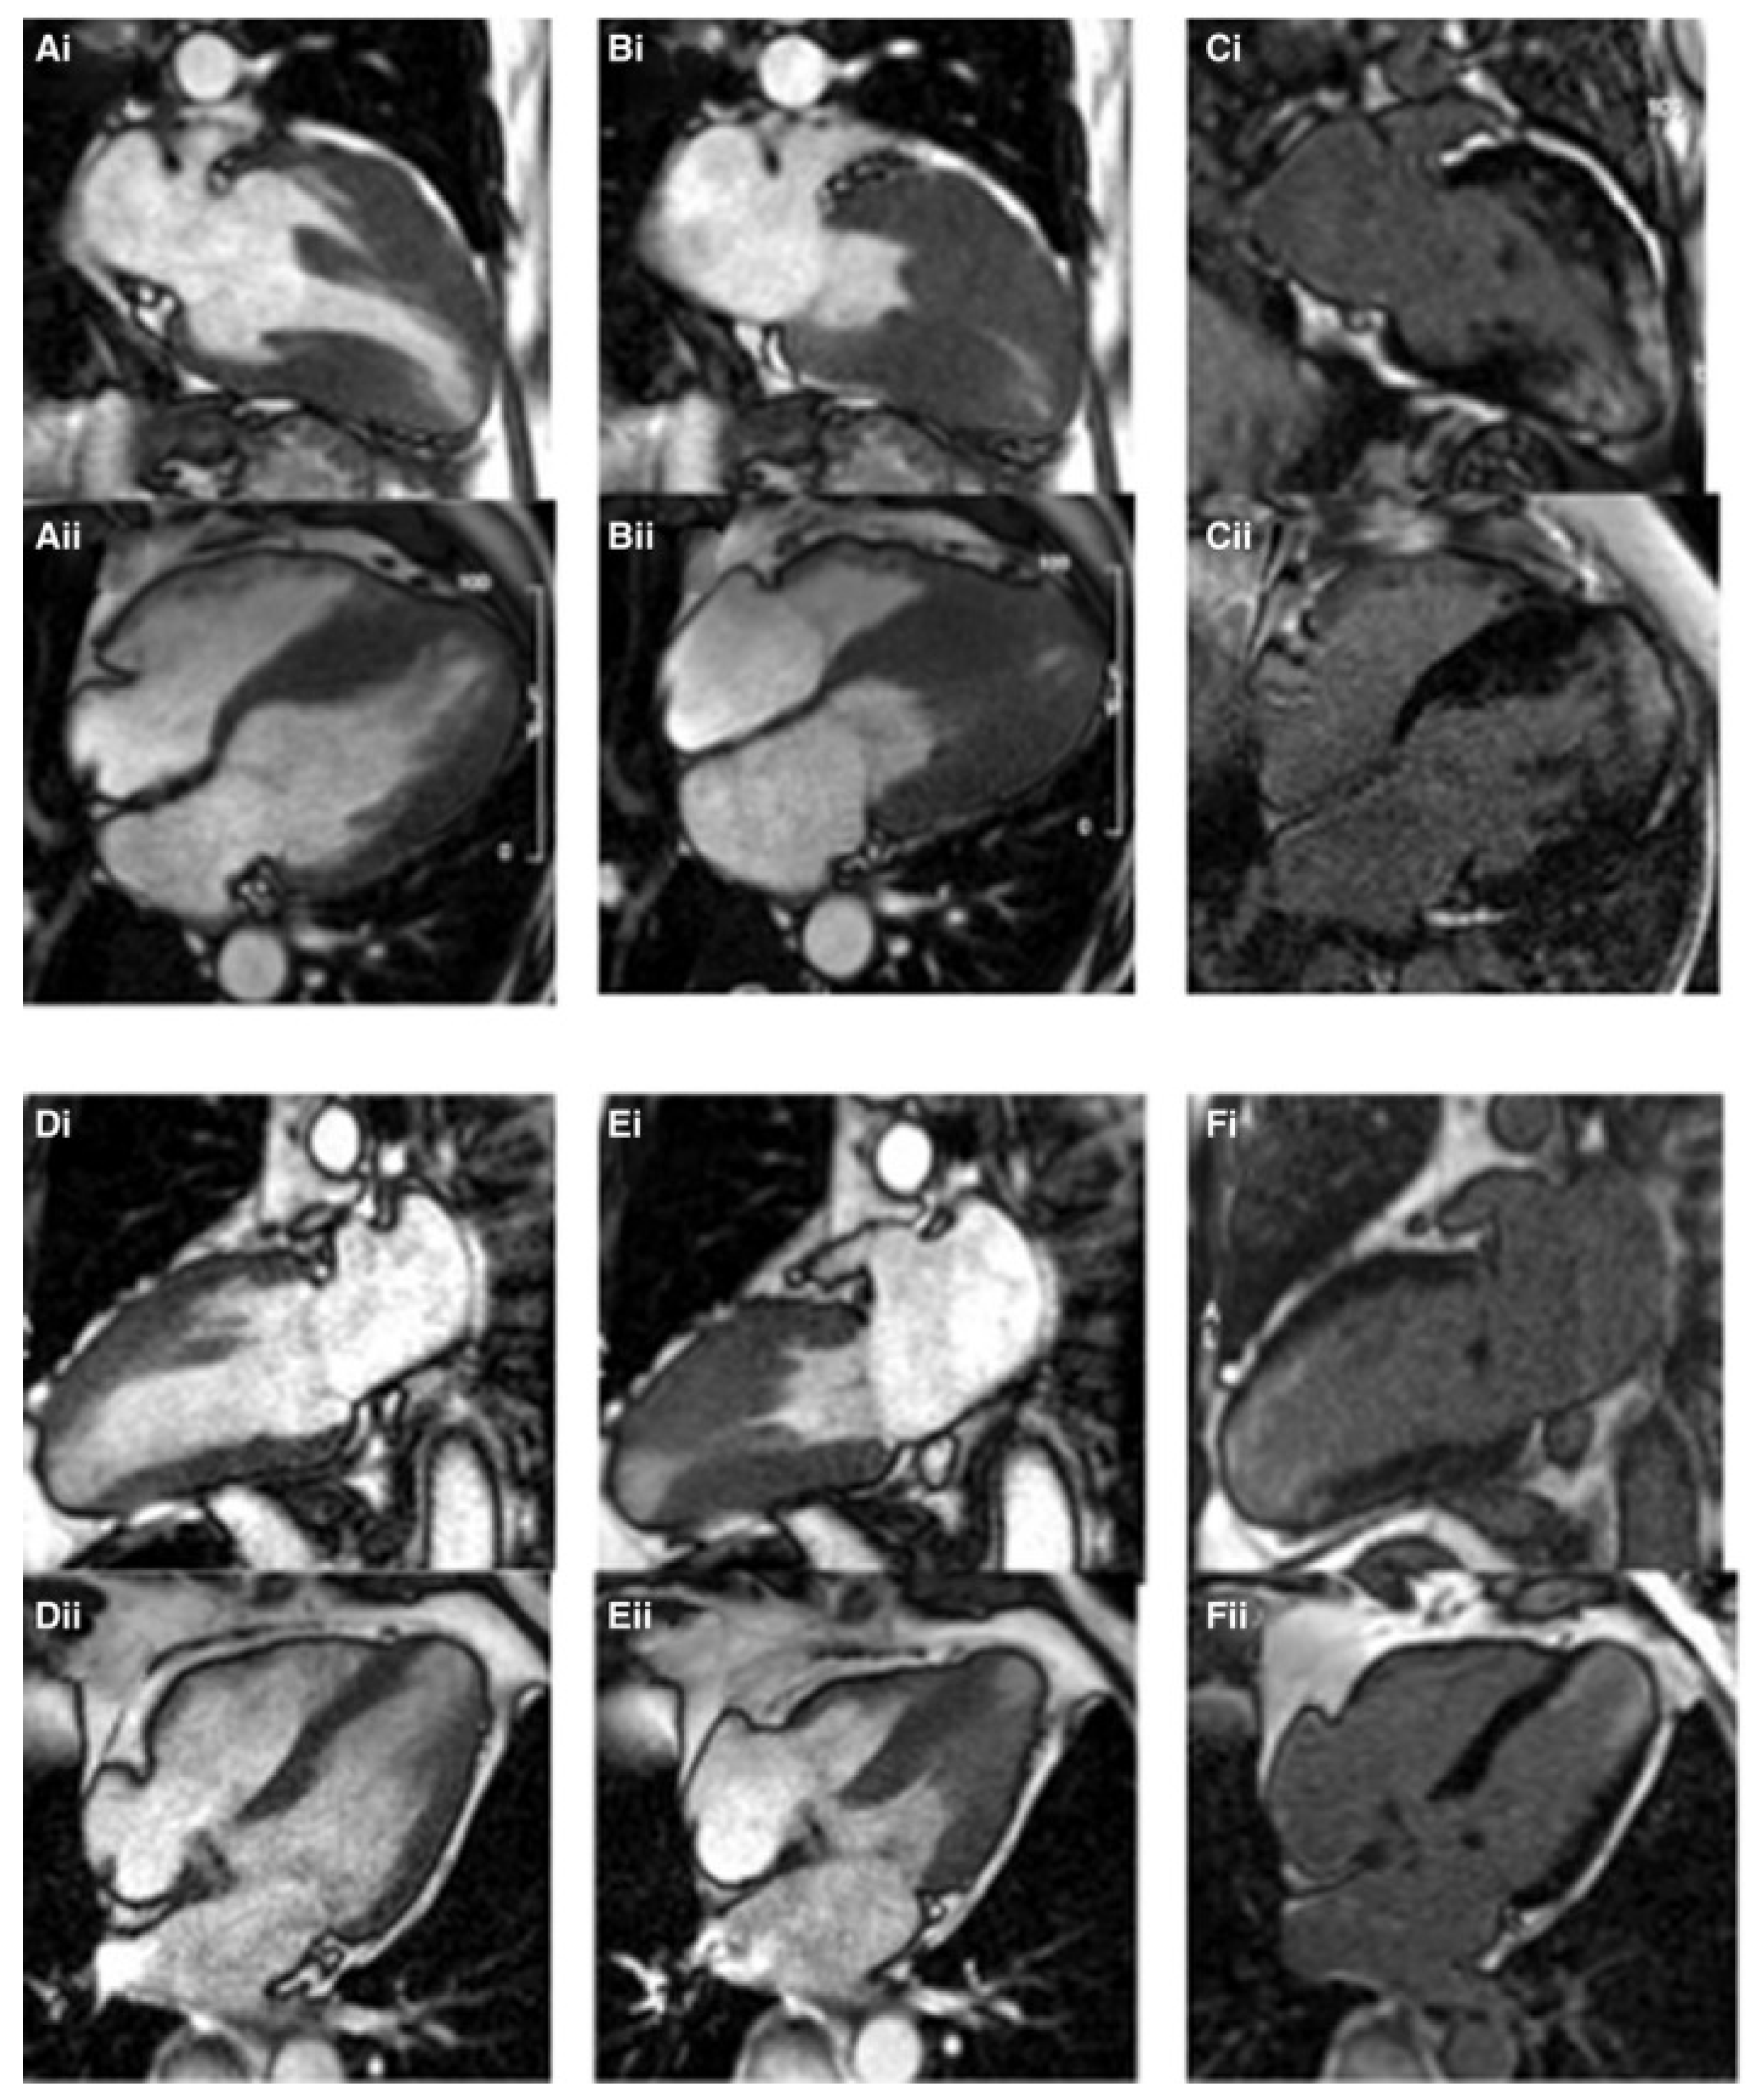

3.2. CMR Evaluation of Focal Hypertrophic Cardiomyopathy

6. Special Considerations in Children

- Chaowu, Y.; Shihua, Z.; Jian, L.; Li, L.; Wei, F. Cardiovascular Magnetic Resonance Characteristics in Children with Hypertrophic Cardiomyopathy. Circ. Heart Fail. 2013, 6, 1013–1020. [Google Scholar] [CrossRef]